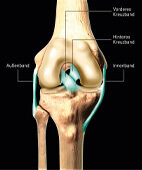

Wichtige Bänder des Knies (Blick von vorne auf das rechte Kniegelenk. Für die Vergrößerung bitte auf die Lupe oben links klicken!)

Das Kniegelenk wird durch mehrere Bandstrukturen stabilisiert: das Außenband, das Innenband, das vordere und das hintere Kreuzband. Vor allem bei Sportunfällen können diese Bandstrukturen stark überdehnt werden und teilweise oder ganz reißen (Bänderriss, Bandruptur). Es kann nur zum Einriss eines einzelnen Bandes kommen (isolierte Ruptur), häufig sind aber mehrere Strukturen betroffen, es findet sich dann auch oft eine Meniskusverletzung. Insbesondere Sportarten mit einem fixierten Fuß wie Skifahren oder Fußballspielen mit Stollenschuhen stellen ein erhöhtes Risiko dar.